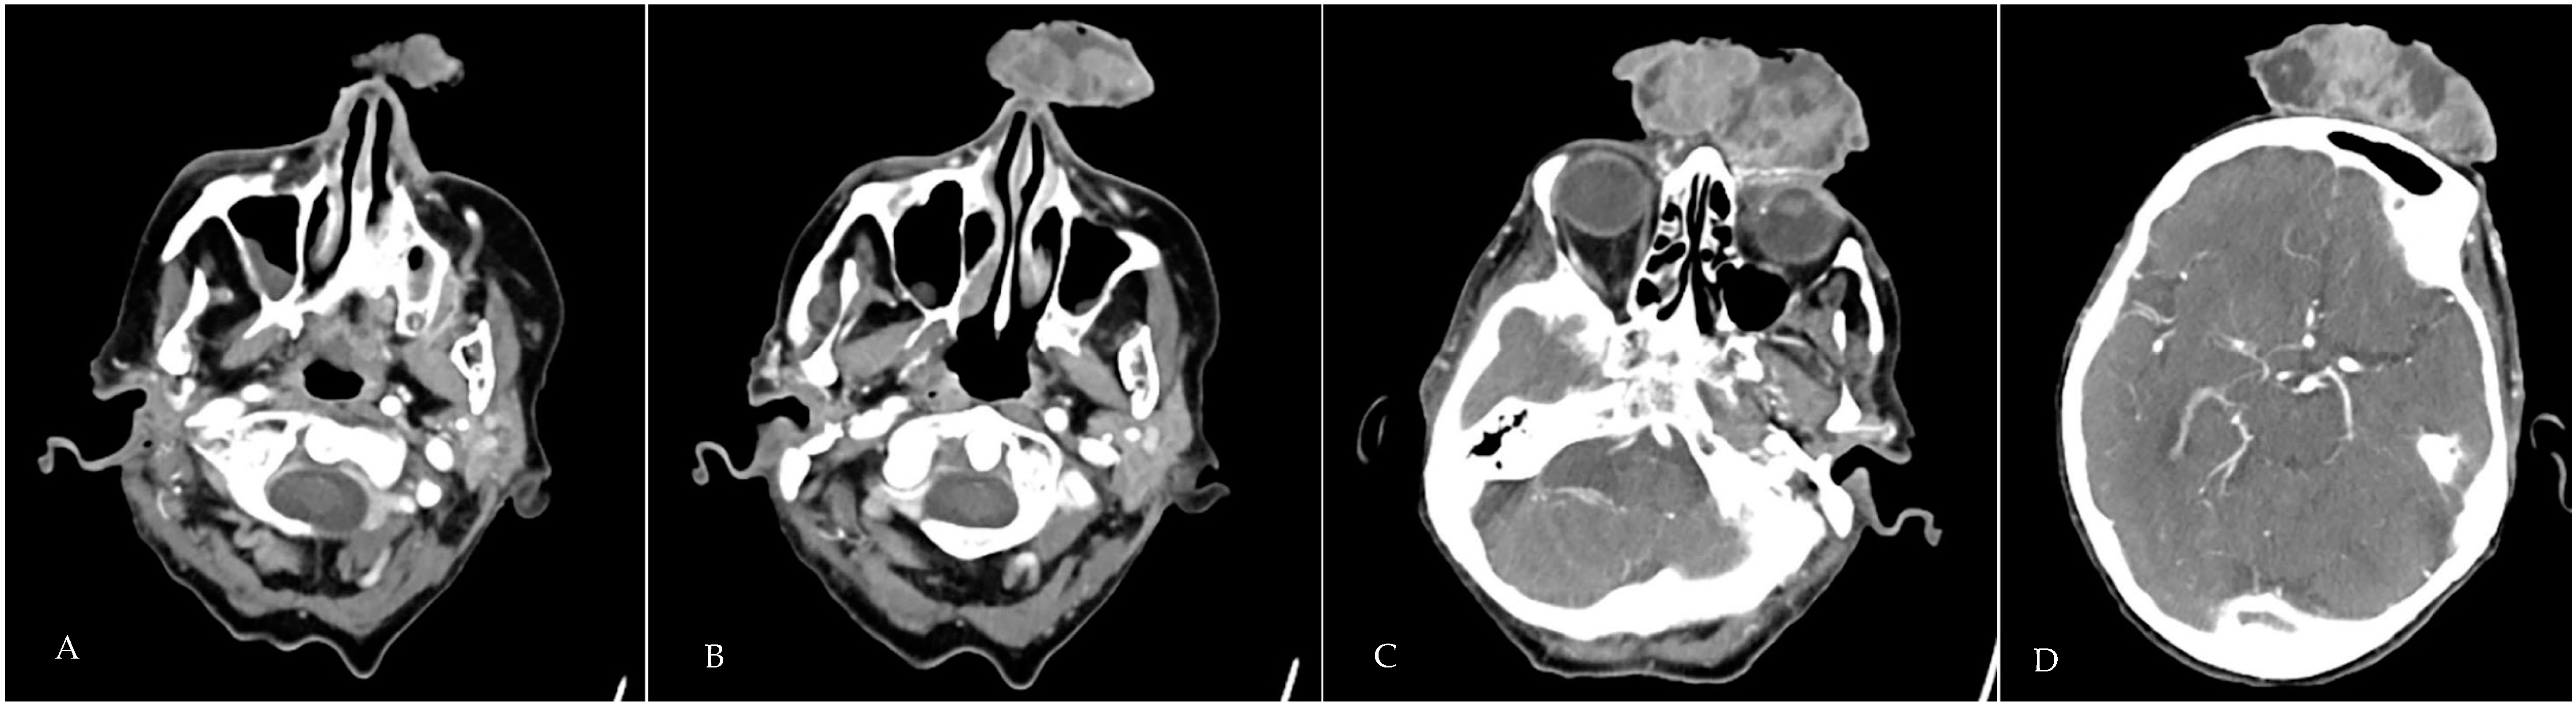

2. Case Presentation